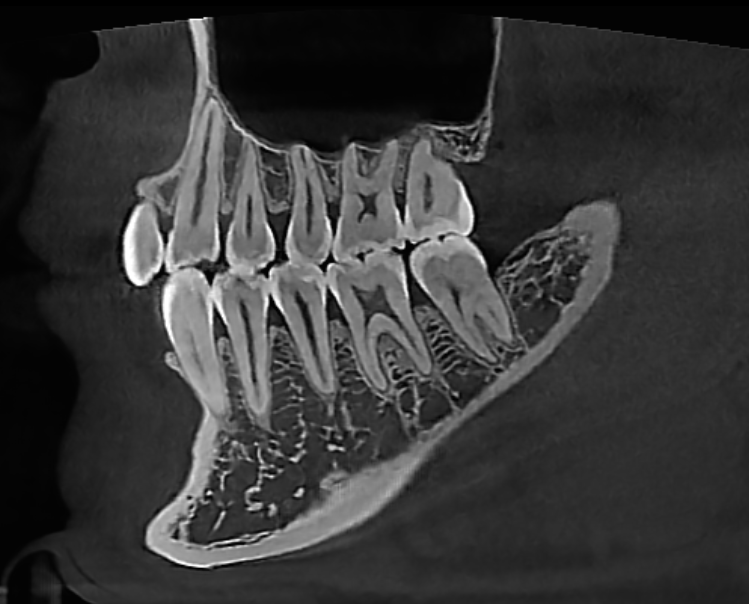

The Dentri MAX is the flagship model from HDX WILL, with the largest avail max FOV at 18x16.5, suitable for a wide scope of uses including advanced implantology, endodontics, orthodontics, orthognathic, bilateral TMJ & airway studies.

Adaptive Exposure Control reduces radiation emission corresponding to the thickness of the object up to 50%. Precision MAR (Metal Artifact Reduction) algorithm ensures the clearest diagnostic images even in presence of metallic objects.